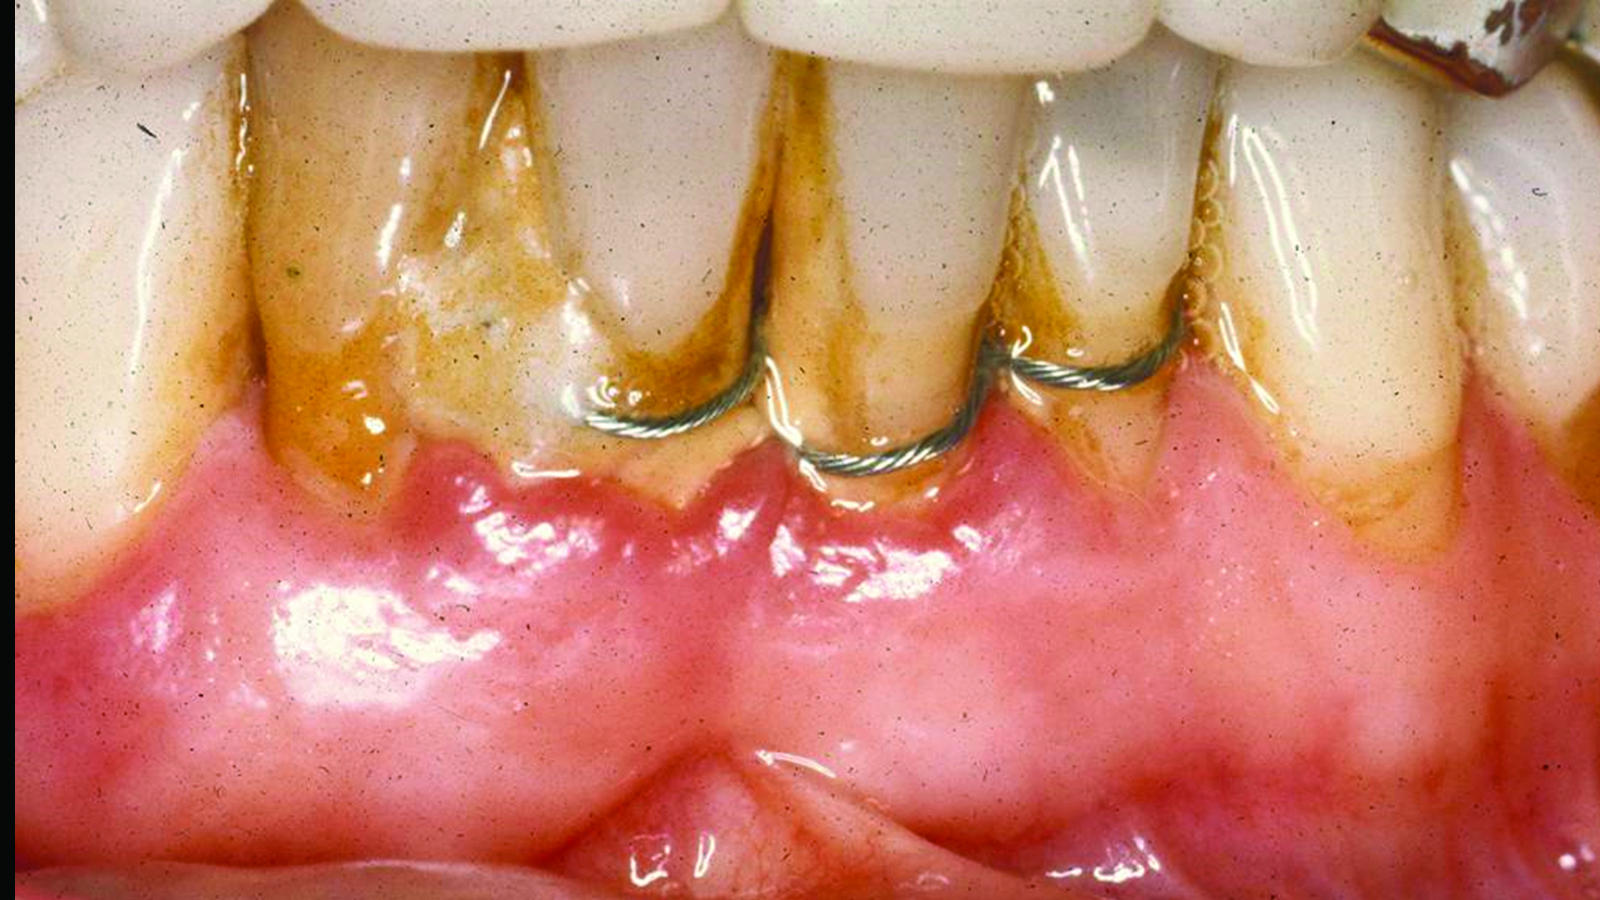

Fig 4. Case 1. Initial presentation of a patient with periodontitis (teeth Nos. 22 through 27). Generalized pocket depths of 5 mm to 6 mm were present.

Figure 4

Fig 7. Case 2. Initial presentation of a patient with periodontitis (teeth Nos. 22 through 27). Generalized pocket depths of 6 mm to 7 mm were present, with wire splint on teeth Nos. 23 through 25.

Figure 7

Fig 8. Initial radiograph of the Case 2 patient, teeth Nos. 22 through 27. Fig 9. SRP resulted in the elimination of inflammation and remaining probing depths of 2 mm to 3 mm in Case 2 patient, 3 months post-therapy. (Fig 4 through Fig 9 are courtesy of Dennis Tarnow, DDS.)

Figure 8

Fig 9. SRP resulted in the elimination of inflammation and remaining probing

depths of 2 mm to 3 mm in Case 2 patient, 3 months post-therapy.

(Fig 4 through Fig 9 are courtesy of Dennis Tarnow, DDS.)

Numerous publications emphasize that oral hygiene and SRP to remove bacterial biofilms and calculus are essential facets of nonsurgical periodontal therapy.39-42 Subsequent to treatment, clinical signs of gingival inflammation (eg, redness), BOP, and probing depths are significantly reduced around single- and multi-rooted teeth (Figure 4 through Figure 9).41,42 A direct relationship has been reported between changes in clinical attachment level (CAL) and probing depth compared to initial pocket depth. The greatest gain of CAL and probing depth reduction occurs at locations with deep pockets (≥7 mm).40-42 The following clinical effects were noted after SRP: mean probing depth reductions at shallow pockets (1 mm to 3 mm), moderate sites (4 mm to 6 mm), and deep sites (>7 mm) were, respectively, 0.03 mm, 1.29 mm, and 2.16 mm.40 The average alterations in CAL for shallow, moderate, and deep probing sites were -0.34 mm (loss of CAL), 0.55 mm, and 1.19 mm, respectively (gain of CAL in the latter two groups).40 Root planing causes CAL loss at shallow probing sites (1 mm to 3 mm),40,42 because it removes cementum where Sharpey's fibers insert into the tooth.43 Proye et al showed recession may occur 1 week after root planing while a gain of CAL is seen in 3 weeks.44 These data indicate that patient alterations in probing depth and CAL may be reassessed 3 to 4 weeks after root instrumentation.